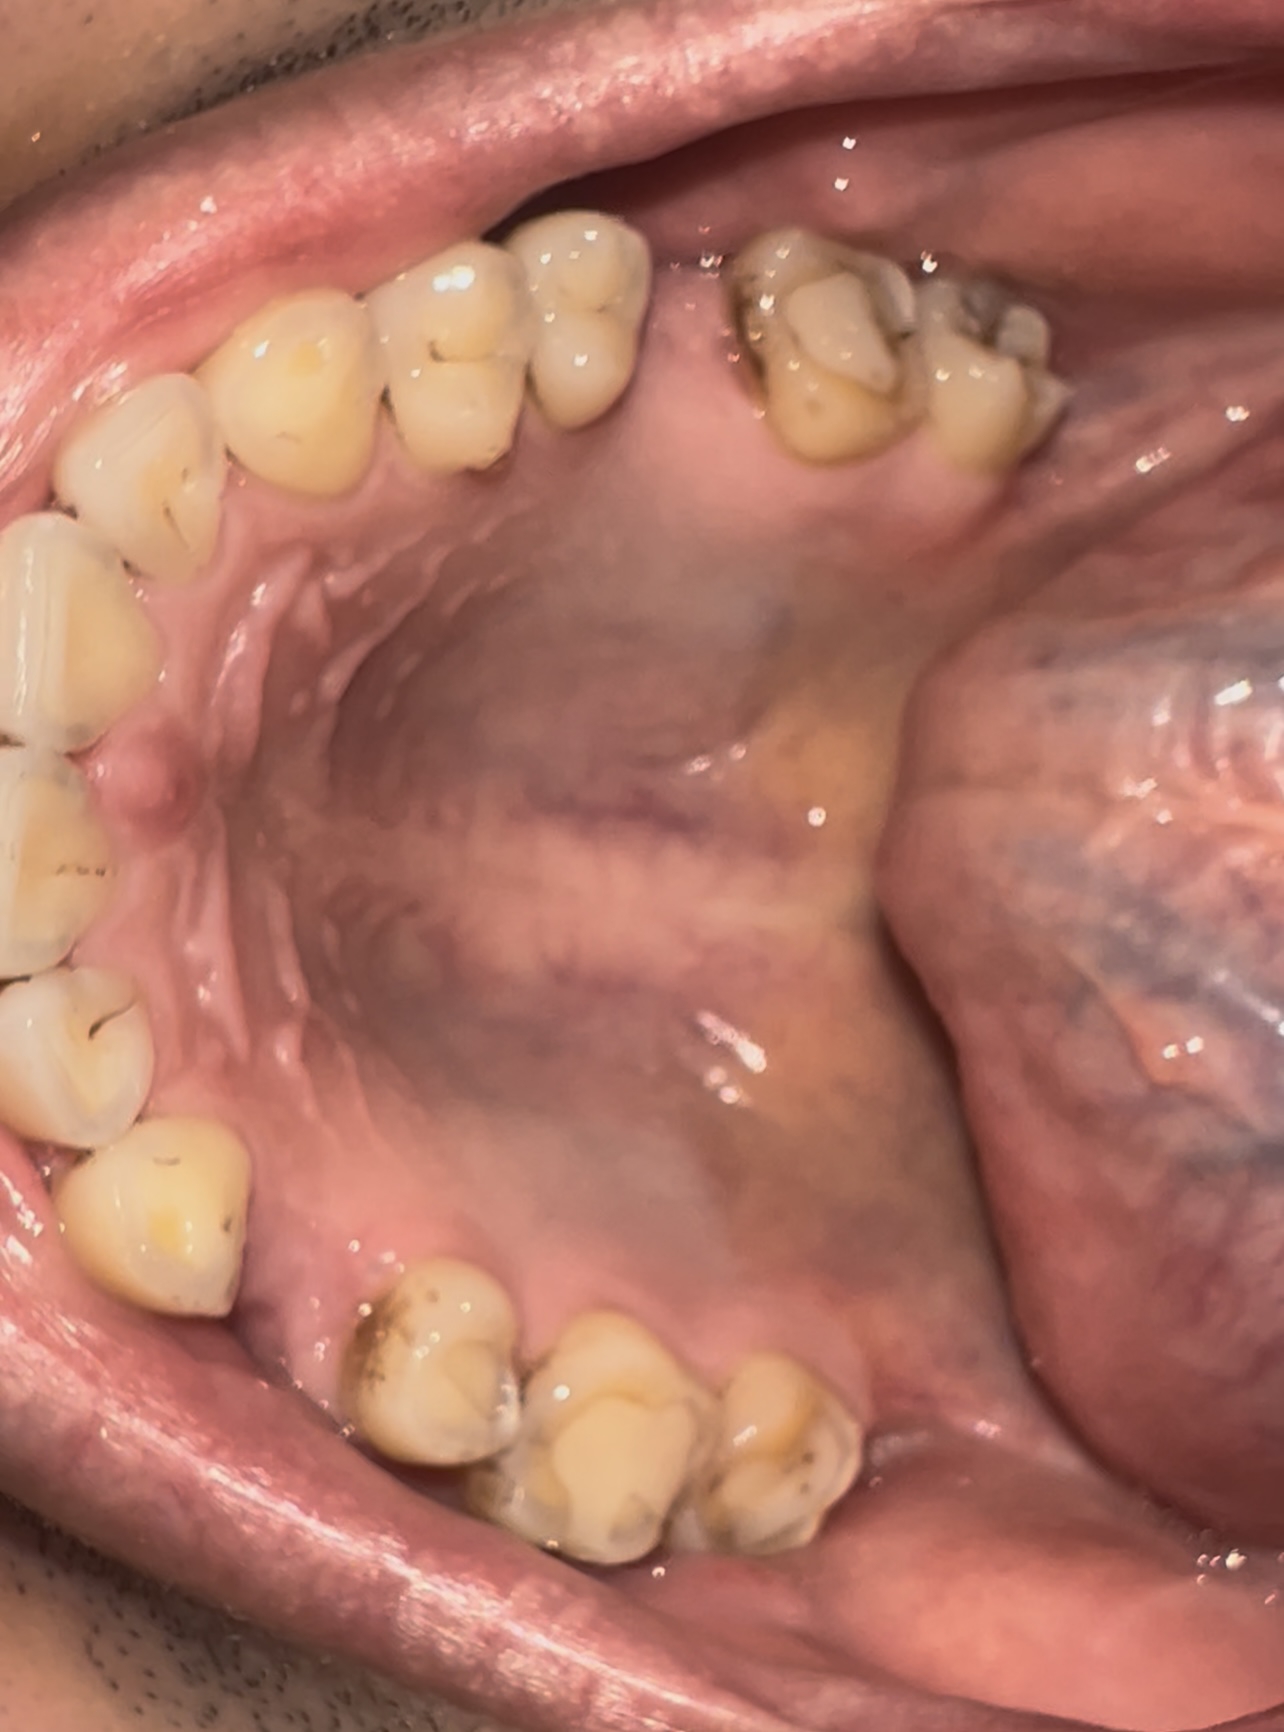

Аноним 08/08/25 Птн 06:11:54 1635233 32

1759678455236.jpg 1558Кб, 2536x3256

2536x3256

1759678455268.jpg 1853Кб, 2252x3434

2252x3434

1759678455308.jpg 217Кб, 1056x1126

1056x1126

1000076562.jpg 534Кб, 1920x1440

1920x1440

1759678455314.jpg 479Кб, 1920x1440

1759678455331.jpg 508Кб, 1920x1440

1759678455339.jpg 562Кб, 1920x1440

Насколько все плохо? Сколько готовить?

Живу в Москве, боюсь. Так что придется искать тех, кто с наркозом работает.